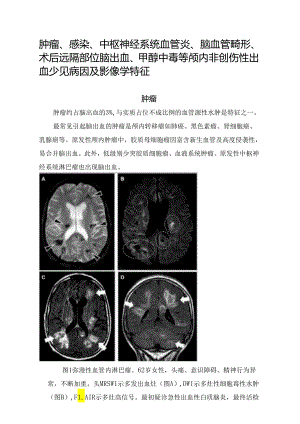

肿瘤、感染、中枢神经系统血管炎、脑血管畸形、术后远隔部位脑出血、甲醇中毒等颅内非创伤性出血少见病因及影像学特征肿瘤肿瘤约占脑出血的3%,与实质占位不成比例的血管源性水肿是特征之一。最常见引起脑出血的肿瘤是颅内转移瘤如肺癌、黑色素瘤、肾细胞癌、乳腺癌等。原发性颅内肿瘤中,胶质母细胞瘤因富含新生血管及高度侵袭性,易合并脑出血。此外,低级别少突胶质细胞瘤、血液系统肿瘤、原发性中枢神经系统淋巴瘤也出现脑出血。图1弥漫性血管内淋巴瘤。62岁女性,头痛、意识障碍、精神行为异常,不断加重。头MRSWI示多发出血灶(图A),DWI示多灶性细胞毒性水肿(图B),F1.AIR示多灶高信号。最初疑诊急性出血性白质脑炎,最终活检证实为弥漫性B细胞淋巴瘤。感染当脑出血患者合并感染证据时,应警惕感染继发脑出血的可能(图2)。神经系统受累是感染性心内膜炎最常见的心外并发症;其中,脑出血仅次于脑梗死排第2位。单纯疱疹病毒脑炎(常见)、脑脓肿、真菌性动脉瘤、细菌性脑膜炎(约1.9%)也可出现脑出血。图2感染性心内膜炎合并脑出血。53岁患者,疲劳、发热,确诊感染性心内膜炎。突发右额顶脑出血、枕部出血、蛛网膜下腔出血(图A),大脑中动脉M2段狭窄(图B,白箭头),可见管壁强化(图C),CTA(图D)及MRA(图E)可见不规则真菌性动脉瘤(箭头),枕部血肿内可见真菌性动脉瘤强化影(图F)o中枢神经系统血管炎中枢神经系统血管炎是脑出血的少见病因,分为原发性及继发性。常见的继发性病因包括水痘-带状疱疹病毒感染、真菌感染、ANCA相关血管炎、白塞病等。原发性中枢神经系统血管炎多累中小动脉,影像学可表现为多灶性脑缺血(约50%)、白质高信号、微出血,少见情况下出现脑出血(图3)。考虑应注意与可逆性后部脑病综合征PRES及可逆性脑血管收缩综合征RCVS鉴别。图3原发性中枢神经系统血管炎。57岁女性,轻微头痛、视物模糊。头CT示左顶叶出血(图A);头MR示弥漫性双侧白质高信号,左顶血肿(图B);脑实质多灶性点状增强及软脑膜增强(图C,白箭头);顶动脉强化(图D,圆圈);MRA示多节段血管远端狭窄(图E,黑箭头);SWI示多灶微出血(图F)。最终诊断为原发性中枢神经系统血管炎,激素治疗后症状部分好转。脑淀粉样相关血管炎CAA-ri表现有意识障碍、癫痫发作、快速进展的认知障碍、头痛。头MR可见多发微出血、皮质表面铁沉积。不同于脑淀粉样血管病CAA,CAA-ri可见白质血管源性水肿,病程相对较急。脱髓鞘疾病急性出血性白质脑炎AH1.E及急性坏死性脑炎是罕见的急性脱髓鞘疾病,预后不佳,本病可出现脑出血,尤其双侧丘脑对称性出血性坏死。遗传性脑血管病N0TCH3基因突变所致的CADASI1.可能会导致脑出血,诊断时需注意有无CADASI1.的其他临床表现。此外,其他如HTRAl基因突变、SNORDl18基因突变、G1.A突变等,也可能合并脑出血。当疑诊遗传性脑血管病导致的脑出血时,建议行基因套组(PaneI)检测,而非特定靶基因检测。脑血管畸形约20%的青年非创伤性脑出血是由于脑血管畸形导致,血管成像是诊断本病的主要手段。各种脑血管畸形包括:动脉瘤、硬脑膜动静脉痿、脑海绵状血管瘤、各种动静脉畸形等。可逆性后部脑病综合征PRES及可逆性脑血管收缩综合征RCVSPRES及RCVS机制有相似之处。PRES常见于先兆子痫、移植术后、恶性高血压等情况下。常见表现有脑病、头痛、癫痫发作等。RCVS好发于20-50岁女性,产后或某些药物易诱发,约1/3可合并脑出血。主要表现是头痛、血管成像是多节段血管狭窄(图4)。图4可逆性脑血管收缩综合征。39岁女性,产后2天,突发反复雷击样头痛伴意识障碍。头CT示脑出血(图A),CTA示弥漫性血管狭窄(图B,白箭头),9天后复查血管狭窄程度较前加重(图C,白箭头),3月后复查MRA各处血管狭窄完全缓解(图D)o静脉窦血栓形成CVST约40%的静脉窦血栓形成患者可能会合并脑出血,尤其脑叶出血。CVST危险因素有感染、肿瘤、外伤、口服避孕药、围产期等。Moyamoya病烟雾病是一种病因不明的、以双侧颈内动脉末端及大脑前动脉、大脑中动脉起始部慢性进行性狭窄或闭塞为特征,并继发颅底异常血管网形成的一种慢性脑血管疾病。成年患者以自发性脑出血常见,尤其脑室出血(图5)o图5Moyamoya综合征。12岁患儿,脑室出血及脑深部出血(图A);CTP示灌注不对称,右额脑血流量增加(图B);DSA示右大脑中动脉狭窄,局部新生血管侧支形成(图C);远端新生侧支动脉可见动脉瘤(图D)。血液系统疾病脑出血是一些血液系统疾病如血友病、遗传性凝血因子缺乏(如II因子、V因子、VII因子、VIII因子缺乏)等的严重并发症。Sneddon综合征是一种罕见的非炎性症血栓性动脉病,约7%的Sneddon综合征可出现脑出血。术后远隔部位脑出血一种少见情况下,幕上开颅术后可出现手术远隔部位颅内出血,约0.08%-0.6%o甲醇中毒脑出血是甲醇中毒的典型并发症,饮用假酒可导致甲醇中毒,症状包括疲乏、恶心、呕吐、腹痛、头痛、呼吸困难、意识障碍等。可伴双侧对称性白质、壳核梗死,后期可出现上述区域出血,尤其壳核。吸毒/放疗可卡因明确与脑出血相关,海洛因、安非他命等少部分情况下也可导致脑出血。放射性脑血管病是放疗的晚期并发症,脑动脉受累后呈双侧非典型扩张、狭窄或装完,可表现为缺血或颅内出血。脑出血的机制可能是动脉瘤、动静脉畸形或继发侧支代偿新生血管破裂。下表中列出中脑出血少见病因的临床警示征象(RedFlags):击样头痛RCVS.CVST.SAH发热中枢神经系统感染,感染性心内膜炎.系统性血管炎伴中枢神经系统损害肿痛活跃期脑转移,原发性中枢神经系统肿痛、严重凝血功能异常同时合并脑缺血及脑出血CVSrRCVS.PRES,感染性心内膜炎、中枢神经系统血管炎、DADA2病脑水肿脑转移,CVST.PRES多灶性脑出血脑转移CVST.RCVS.中枢神经系统血管炎,感染性心内膜炎软脑膜强化中枢神经系统血管炎.脑膜炎脑出血合并SAH动脉掖.CVST.RCVS,硬脑膜动静脉瘦DAVF.动静脉畸形AVM药物PRES.RCVS,可卡因相关血管炎精神症状遗传性脑小血管病、中枢神经系统血管炎合并较严重白质高信号.腔隙遗传性脑小血管病皓床影像征象脑出血痛因